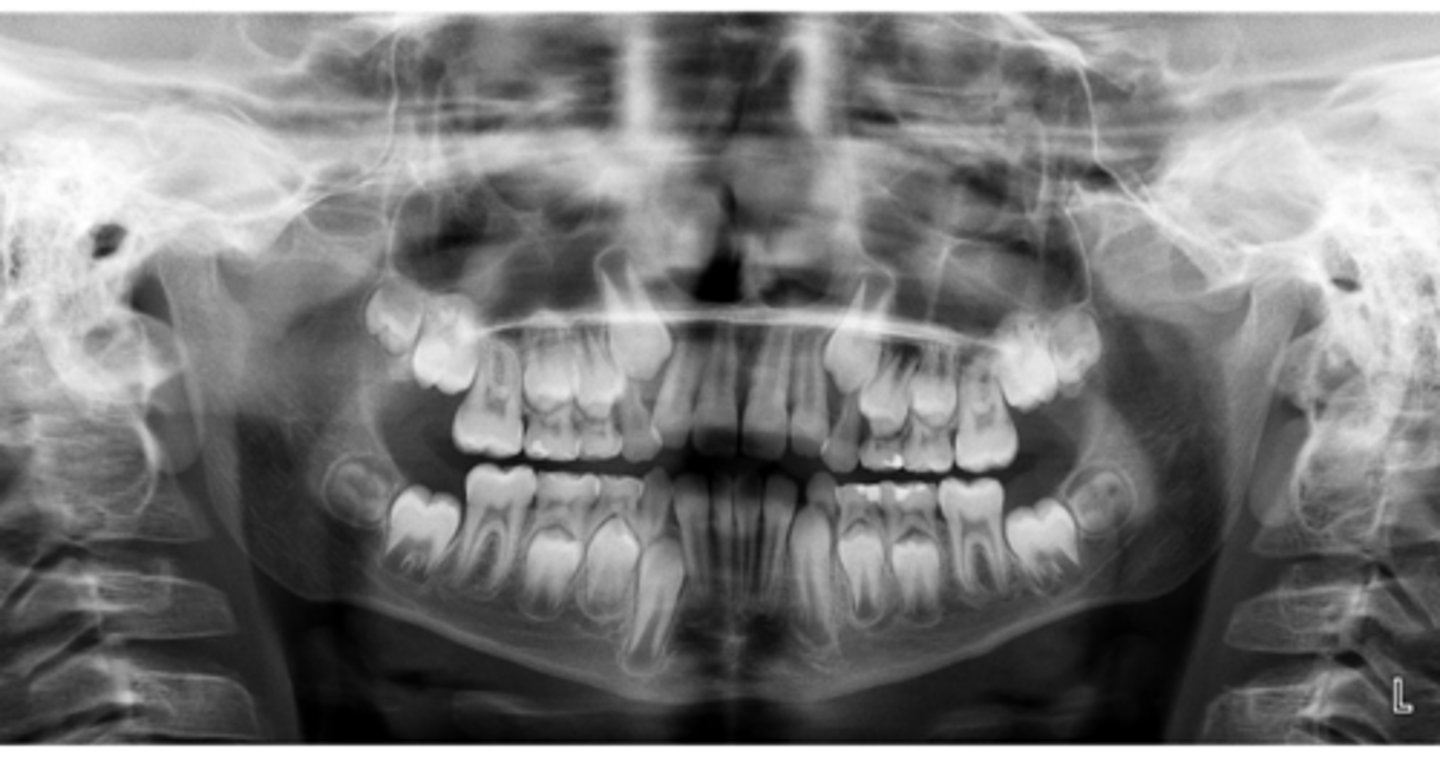

Class II skeletal (very light)

What type of skeletal malocclusion is this patient?

Hypodivergent

Are the hyper-, hypo-, o normo- divergent?

proclined

Maxillary incisors are?

Class II

Hyperdivergent

Class I

Normodivergent

No

Are the maxillary incisors proclined/flared?